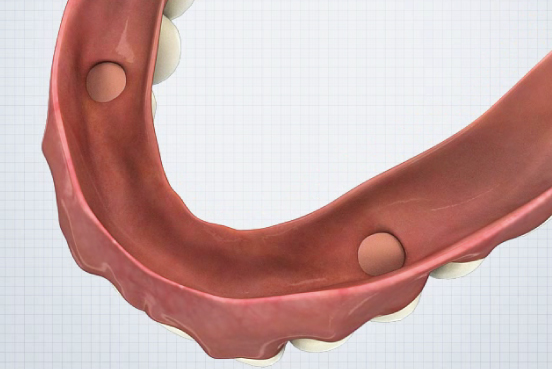

- Denture Hole 위치 파악- Housing 공간 확보

- Vent Hole 형성

- Denture Hole 위치 파악- Housing 공간 확보

- Vent Hole 형성